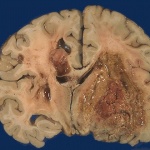

Gli  sfingolipidi bioattivi giocano ruoli fondamentali nella carcinogenesi attraverso la loro capacità di regolare percorsi di morte cellulare programmata, risposte allo stress, l’immunità  e l’infiammazione. L’impatto del metabolismo degli sfingolipidi è particolarmente importante nel tumore del colon, poichè le cellule epiteliali intestinali sono esposte a metaboliti sfingolipidici generati dalla rottura degli sfingolipidi alimentari. S1P, il prodotto di degradazione finale degli sfingolipidi, è un lipide di segnalazione pro-infiammatoria che promuove la crescita cellulare e la carcinogenesi. Durante la trasformazione maligna e la progressione del cancro del colon, cambiamenti genetici avvengono nei tessuti intestinali, tra cui un aumento dell’enzima che genera S1P e una diminuzione S1P liasi (SPL), l’enzima che catalizza la degradazione S1P. Questi cambiamenti portano ad accumulo di S1P nella mucosa intestinale.

Per esplorare l’impatto dell’ accumulo di S1P sulle infiammazioni e carcinogenesi, i ricercatori hanno prodotto un modello di topo privo di SPL nei tessuti intestinali. Hanno poi caratterizzato le sue risposte utilizzando un modello chimico-indotto del tumore del colon-colite associato. Rispetto ai topi di controllo, i topi mutati sono risultati esposti a più infiammazione e d una maggiore incidenza di tumori in questo regime. Utilizzando una combinazione di esperimenti su topi e coltura cellulare, gli scienziati hanno identificato una cascata di passaggi a valle di S1P che portano infine al silenziamento di due proteine ​​tumorali le cui funzioni sono di proteggere contro la formazione del cancro.  In contrasto con gli effetti promotori del cancro di S1P, i ricercatori hanno dimostrato che la soia o di un impianto di sfingolipidi chiamati sphingadienes non possono essere metabolizzati, mentre aumentando il metabolismo di S1P, aumentano i livelli di SPL nei tessuti intestinali.